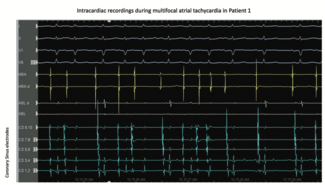

Dr Methachittiphan and colleagues describe successful ablation of incessant multifocal atrial tachycardia in 2 patients—one with severe obstructive sleep apnea and a second patient with severe fibrotic interstitial lung disease.